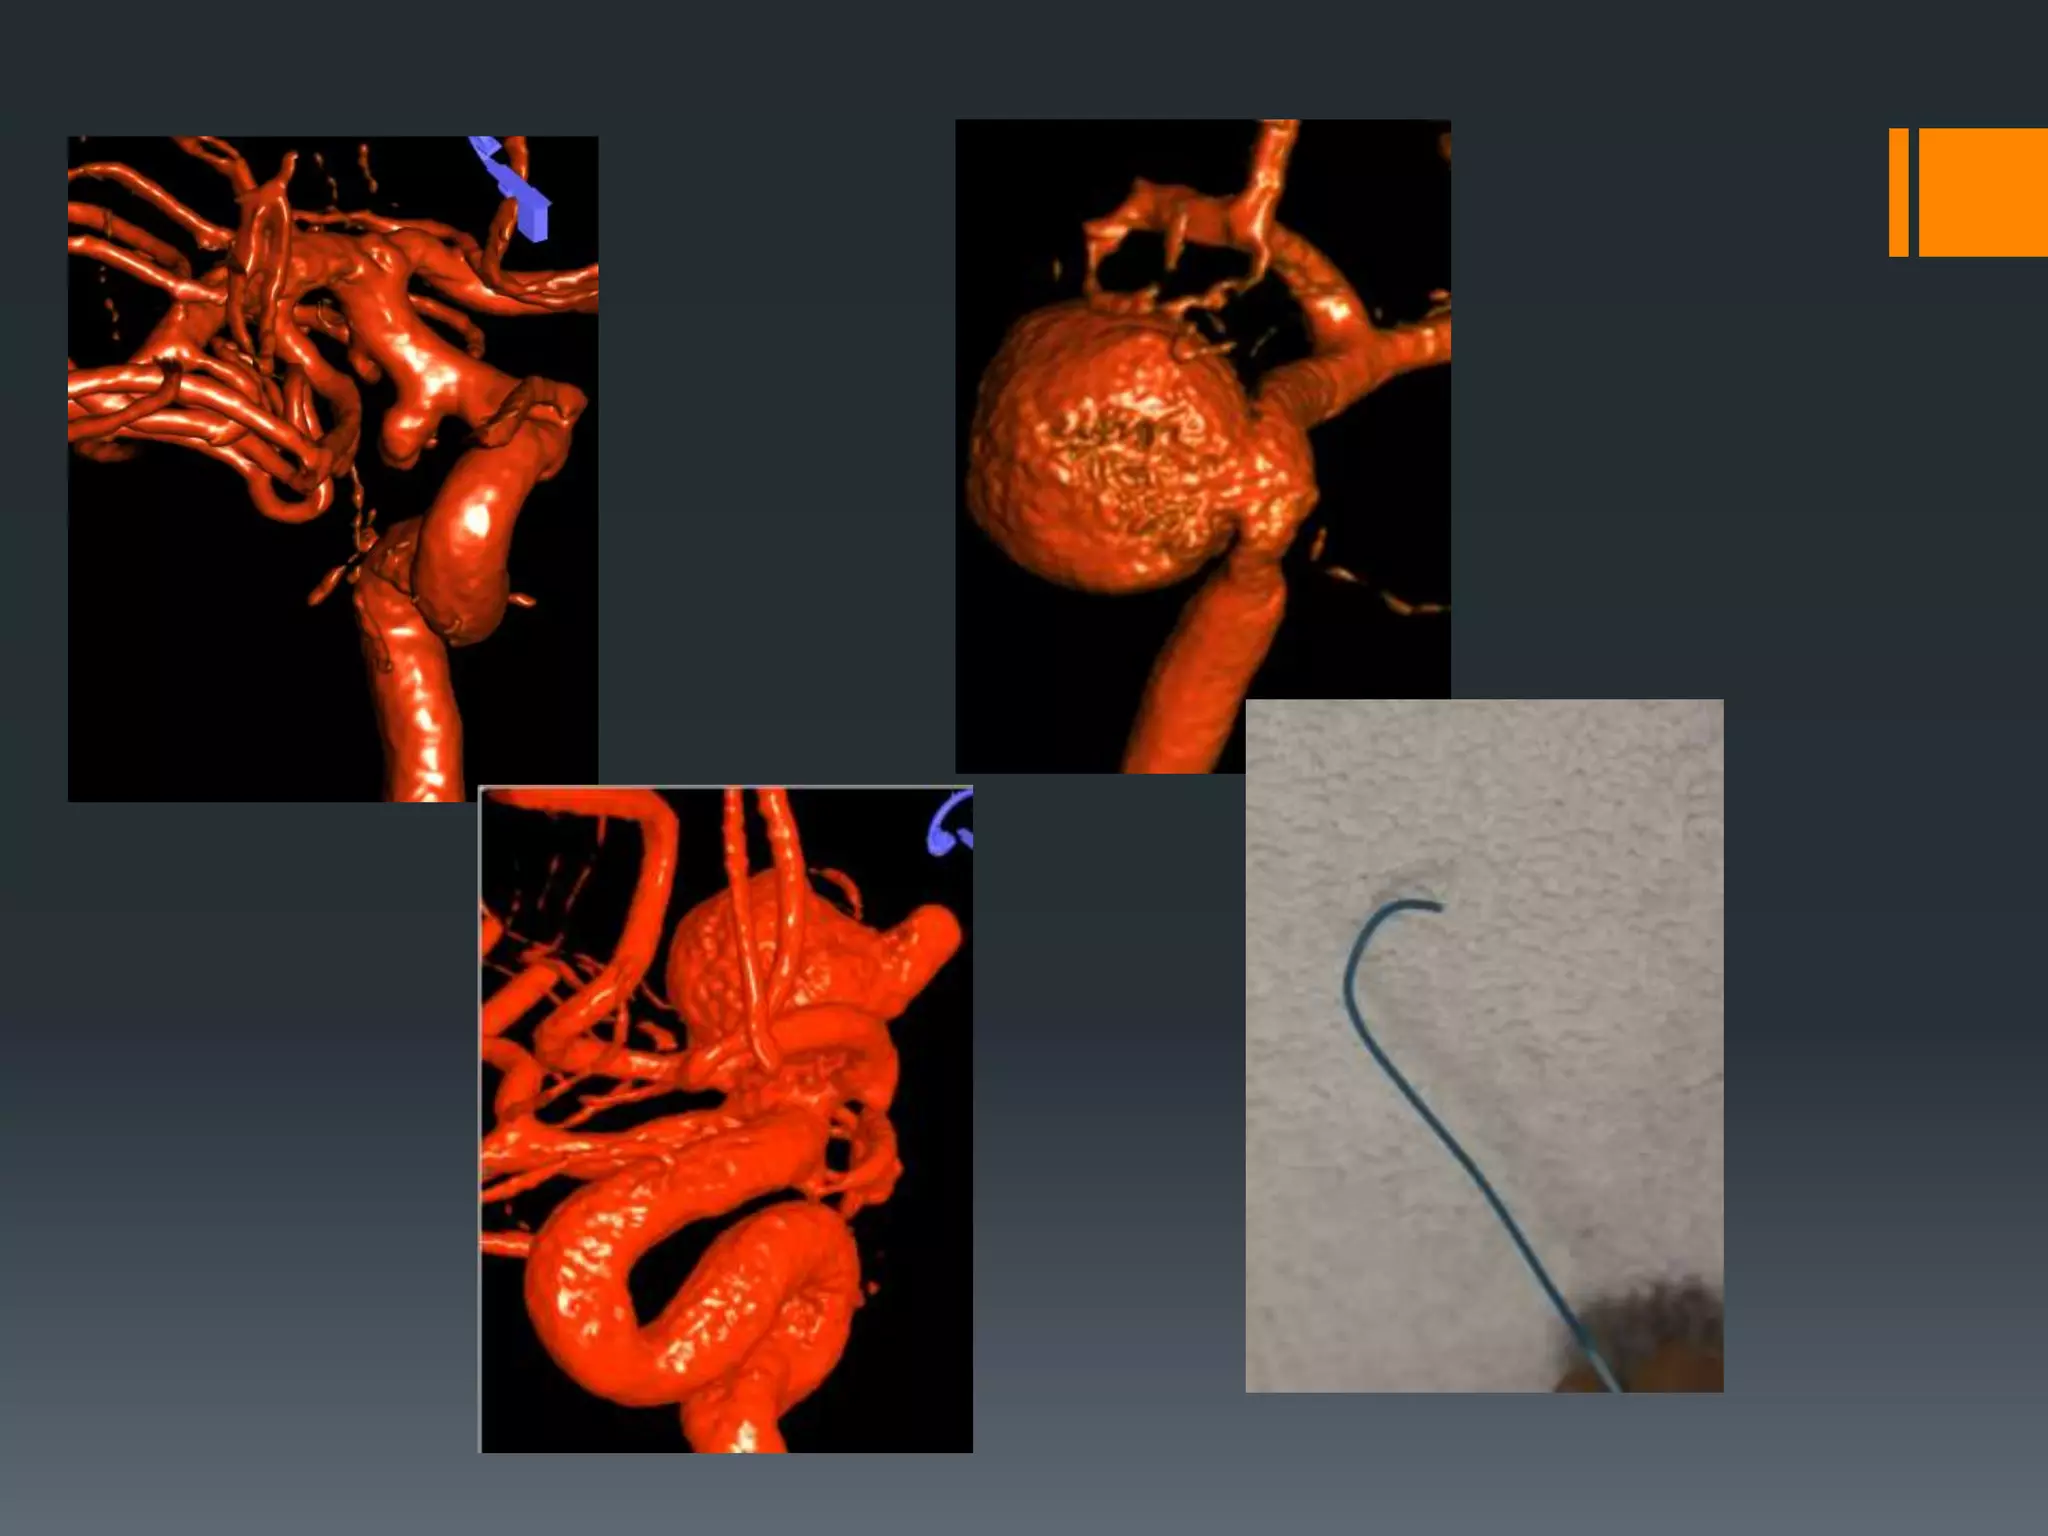

This document discusses tricks and techniques for difficult cannulations during neurointerventional procedures. It outlines strategies for accessing the aortic arch, internal carotid artery (ICA), and areas distal to aneurysms. Long sheaths, distal access catheters, and co-axial techniques are presented as options that have improved cannulation success. Guidance on sheath and catheter selection is provided for different vessel paths. The importance of catheter placement as high as possible in the ICA is emphasized. Reverse curve cannulations are also mentioned. Overall, the document stresses that careful cannulation is critical for procedural success and different strategies may be needed depending on the vessel target.